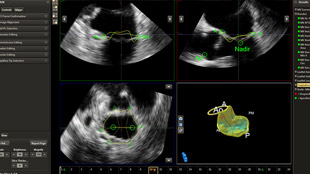

يوفر صمام تاجي المستكشف الحسابات في بضع خطوات سهلة وسريعة.

التخطيط للإجراءات باستخدام البيانات الكمية الموثوقة.